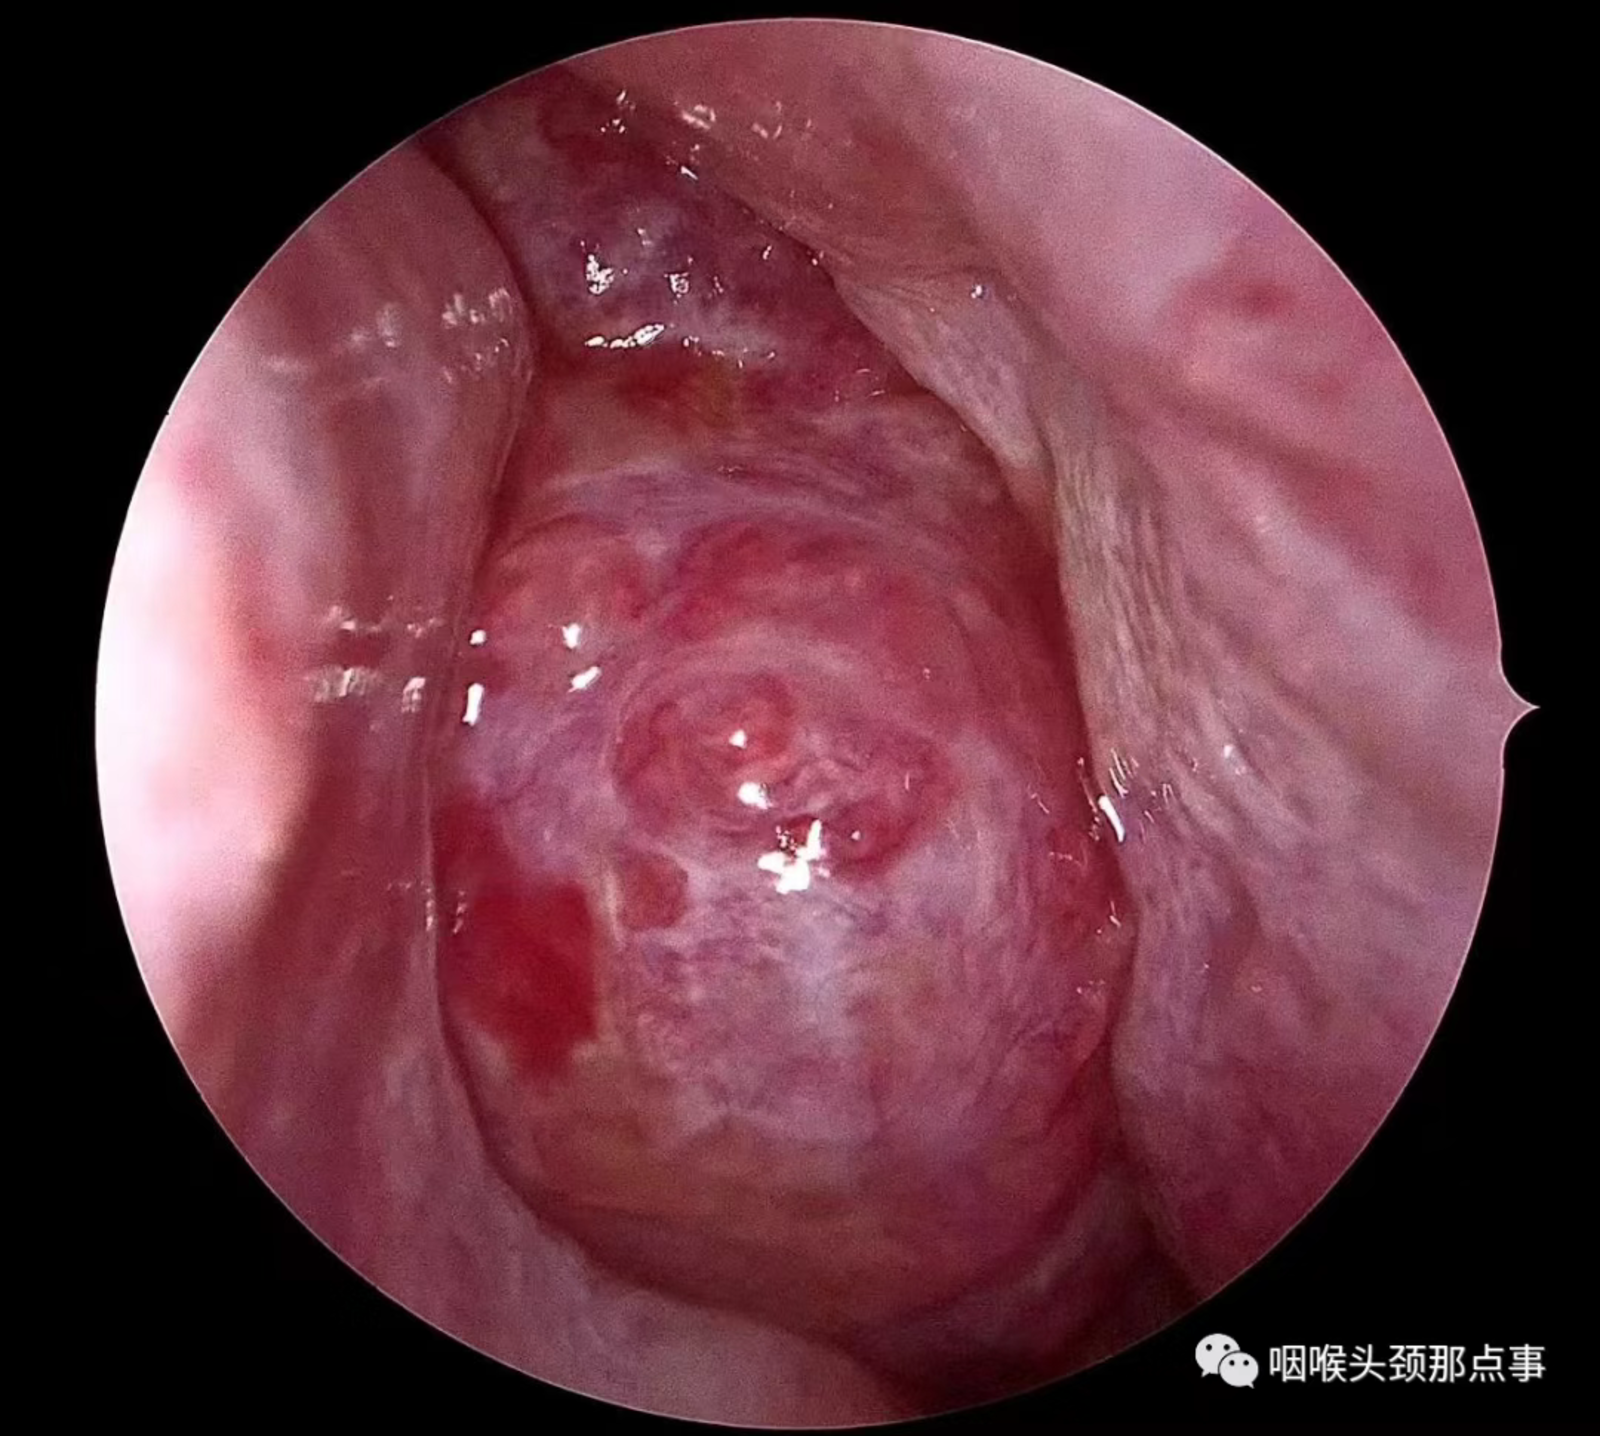

现在随着工业发展及大气污染,过敏性鼻炎患者患病率也明显增高,过敏性鼻炎常表现为鼻甲肿大,苍白水肿,患者鼻塞较明显,鼻音很重,夜间打呼憋气;肥厚性鼻炎也是重要原因之一;再有就是良性的比如鼻息肉、鼻腔乳头状瘤、骨化性纤维瘤等鼻腔堵塞;还有就是鼻腔恶性肿瘤等堵塞整个鼻腔导致的张口呼吸。

鼻腔肿瘤1

鼻腔肿瘤2